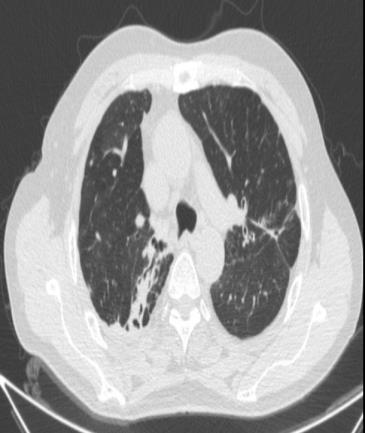

• 右肺中叶病变的临床特征分析(附709例报告)

摘要:目的 探讨右肺中叶支气管异常患者的人口学特征、临床表现、病因、影像学表现和支气管镜下表现。方法 回顾性分析2015年5月-2025年4月于该院在支气管镜检查中表现为右肺中叶异常改变的709例患者的临床资料,统计分析病因和临床特征。结果 709例患者中,男465例,女244例。男患者年龄(63.1±9.1)岁,明显高于女患者的年龄(60.9±11.5)岁,差异有统计学意义(P < 0.05)。临床表现主要包括:咳嗽、气促、咯血、痰中带血和胸痛,9.9%的患者未出现临床症状。根据年龄范围进行分组,将年龄 > 55岁的542例(76.4%)患者纳入高龄组,≤55岁的167例(23.6%)患者纳入低龄组,高龄患者明显多于低龄患者,差异有统计学意义(P < 0.05)。高龄组中,常见的3种病因分别为:肿瘤、炎症和结核。支气管镜下表现为:右中叶新生物、黏膜肥厚或肿胀、管腔狭窄和瘢痕闭塞等。结论 右肺中叶病变的患者采用影像学和支气管镜相结合的方式,对明确病因和指导临床治疗有重要意义。